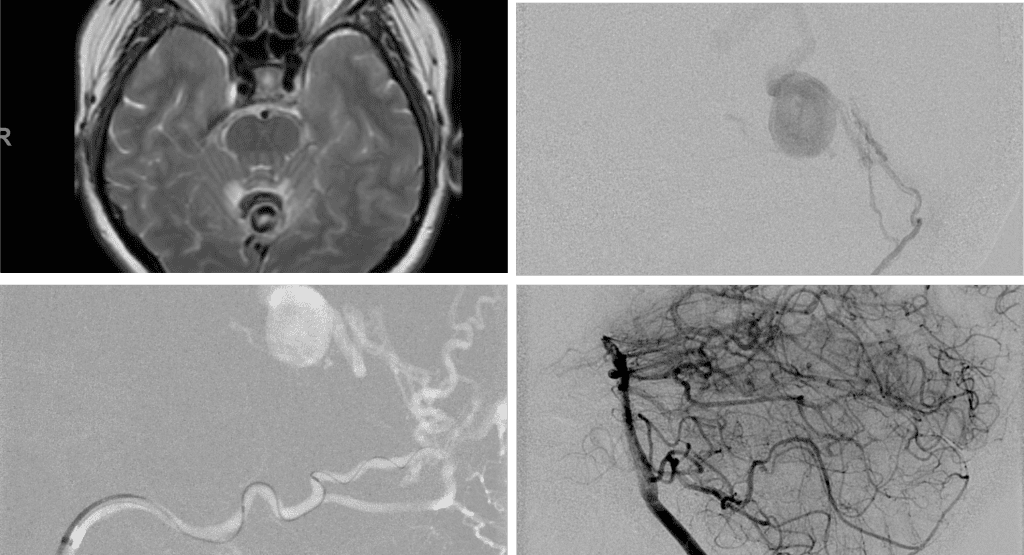

A 55-year-old woman presented with acute onset of severe headache, and possible witnessed seizure. Imaging confirmed intraventricular hemorrhage primarily focused within the fourth ventricle with diffuse subarachnoid hemorrhage within the posterior fossa and along the tentorium as observed on non-contrast CT and MRI of the Brain (Figure 1).

Figure 1. A and B) Non-Contrast CT Axial and Coronal demonstrate large, ruptured Varix/Aneurysm along the Incisura of the posterior fossa which appears to have mixed hemorrhagic components and enhancement on MRI T2 and post contrast imaging (C and D).

No severe neurologic deficits were observed initially. Her cerebral angiogram revealed a high flow Dural arterial venous fistulous malformation of the tentorium supplied by the bilateral external carotid and left vertebral arteries into a large venous varix within the fourth ventricle at the site of the hemorrhage. Deep venous drainage is observed into the Galenic and Straight Sinus of the posterior fossa (Figure 2).

Figure 2. [A] Ruptured Varix/Aneurysm of the Deep Venous Posterior Fossa drainage and AV shunting (arrows) [B] Posterior Meningeal Artery Fistula [C] Right Middle Meningeal Artery Fistula [D] Post embolization Left Vertebral Angiogram demonstrates resolution of the high flow and pressure A-V Shunting following successful embolization with liquid embolic (NBCA).